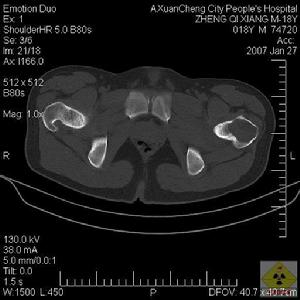

圖2女,11歲。臀肌攣縮症併骨盆傾斜肌肉因變性、壞死,而致纖維化[4]。部分學者還認為與免疫、瘢痕體質、兒童易感因素[5]和遺傳因素等有關。我們對珠江三角洲地區年齡為3~6歲的學齡前兒童,其中男3625名(58.5%),女3375名(41.5%),進行流行病學調查。結果顯示:農村5250名兒童,患臀肌攣縮症218例(4.2%),城鎮950名兒童,患臀肌攣縮症11例(1.1%),農村發病率高於城市;且營養不良、衛生條件差、生活地面不平坦地區發病率高於營養衛生條件好的平原地區。也有報導認為臀肌攣縮症與外傷有關[6],但導致骨盆傾斜的原因尚不明確。鄭啟新[7]認為,臀中肌攣縮導致骨盆傾斜是由於攣縮肌肉組織的“韁繩作用”,即牽拉同側骨盆而對側髂骨前外側端抬高。我們觀察發現,立正時出現骨盆傾斜,使一側足跟離地,而當兩腿分開髖外展時骨盆傾斜消失。本組84例中,有76例為臀小肌攣縮(90%),而臀中肌攣縮僅有36例(43%),因此推測臀小肌攣縮是導致骨盆傾斜的主要原因。2例骨盆傾斜未完全矯正者,當再次手術時發現,骨盆傾斜未完全矯正的原因是第一次手術未松解臀小肌攣縮帶所致。臀中肌和臀小肌均起外展作用,臀小肌的支持力大於臀中肌[8]。根據吳維才等[9]股槓桿理論,髖關節中立位時,額狀面上臀中肌纖維與下肢縱軸線所成角度大於臀小肌,臀小肌起“韁繩作用”力度更大,但由於臀小肌位置深被臀中肌遮擋,所以松解時容易遺漏,因而影響矯正效果。